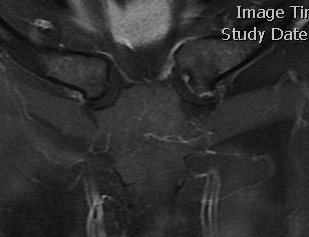

Left posterior SCJ dislocation with pre- and post angiogram

Left posterior SCJ dislocation with pre- and post angiogram

Severe left posterior SCJ dislocation with subclavian vein compression